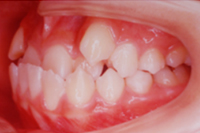

反対咬合(受け口) +八重歯 14歳男子:ブラケット装置(小臼歯抜歯)

治療前

+八重歯 14歳男子:ブラケット装置(小臼歯抜歯)